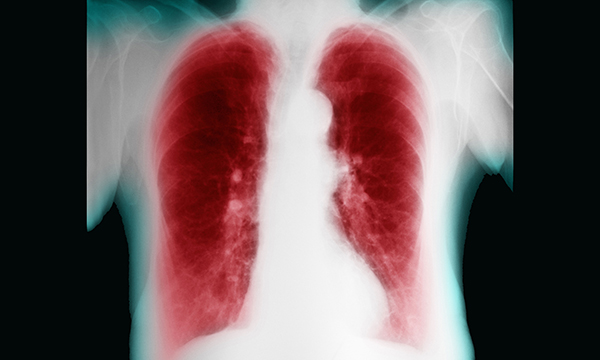

This is a summary of the peer-reviewed article: Abdominal X-rays in children: indications, proced